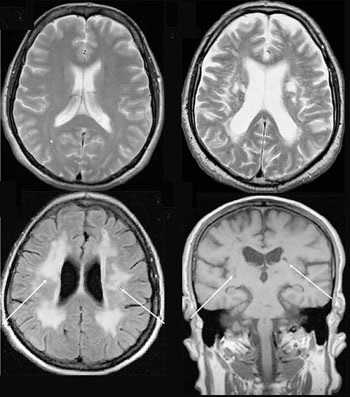

Существенное преимущество МР-томографии перед КТ заключается в том, что она не противопоказана беременным во II и III триместре и совершенно безопасна для детей. В МРТ исследуемая область сканируется в трех проекциях, что позволяет врачу-рентгенологу в полной мере оценить состояние тканей и органов исследуемой области, а высокая контрастность изображения и пространственное разрешение позволяют визуализировать серое и белое вещество головного мозга, оценивать состояние костного мозга и мягких тканей различной локализации. Кроме того, метод МРТ позволяет получать изображения сосудов головного мозга и сосудов шеи без введения контрастного препарата.